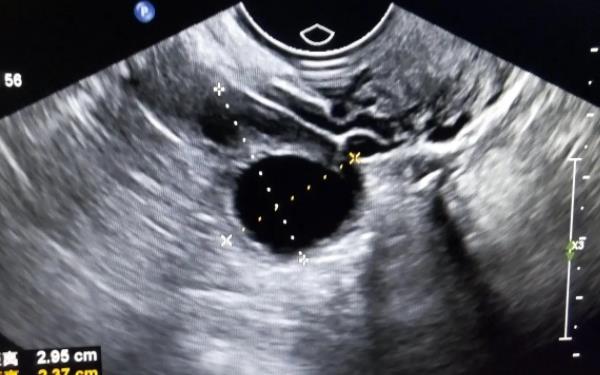

女性的卵泡在发育到成熟的时候是不会塌陷的,而只有成熟之后,卵泡破裂,要从卵巢中排出去的时候,才会出现塌陷的情况,而卵泡如果没有排出体内就塌陷了的话,就说明卵泡在发育的过程中出现了问题,所以女性如果想知道原因最后做个专业的检查,而卵泡如果排出体内的话,主要有以下几点特征: